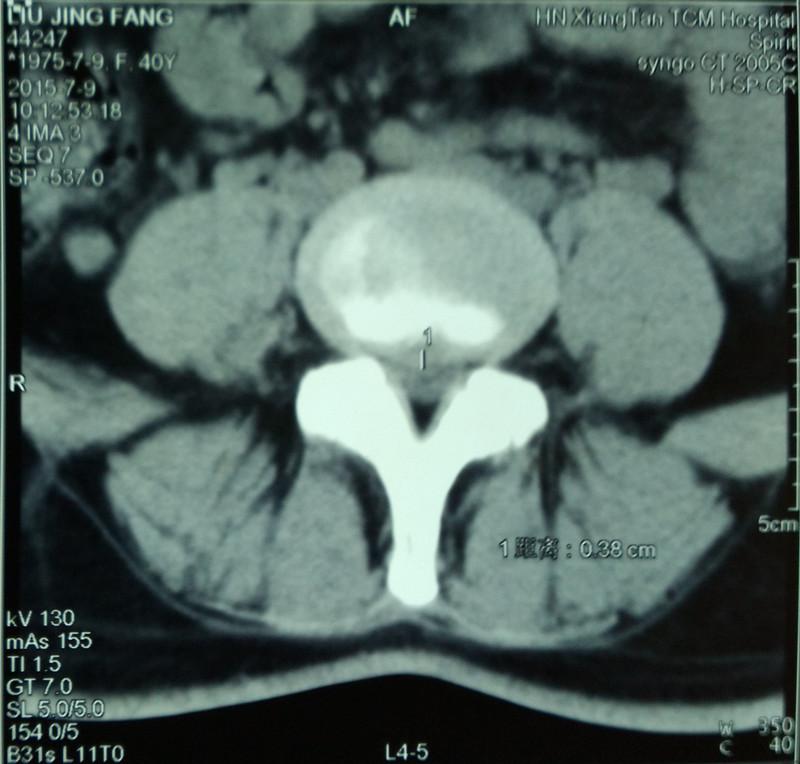

這是我院上周四仇湘中教授坐診時的一例典型門診病例,患者自訴右下肢前外側(cè)放射痛一周來診室就診,并訴5年前有左下肢后側(cè)明顯麻痛史,但經(jīng)治療后近5年一直未復(fù)發(fā)。體格檢查為:L4/5棘突間隙及右側(cè)1.5cm處壓痛,L5/S1棘突及雙側(cè)1.5cm處均無壓痛,右下肢直腿抬高試驗55°陽性,右拇趾背伸肌力稍減弱。仇教授建議患者行腰椎間盤CT檢查(見圖)提示:L5/S1椎間盤向左后方突出約0.5cm,突出物鈣化,神經(jīng)根及硬膜囊稍受壓;L4/5椎間盤中央偏右側(cè)突出約0.38cm,壓痛硬膜囊。乍一看,該患者L5/S1椎間盤突出程度明顯大于L4/5,很容易誤診為L5/S1椎間盤突出癥,但結(jié)合上述病史及體格檢查可以診斷為L4/5椎間盤突出癥,而5年前的診斷為L5/S1椎間盤突出癥。

疑問是該患者5年前的發(fā)作的L5/S1明顯突出,為什么近5年一直未復(fù)發(fā)呢?仔細(xì)閱片可知,L5/S1左側(cè)神經(jīng)所在的側(cè)隱窩明顯狹窄,但神經(jīng)根的位置已明顯向椎管方向移位了,這是典型的受壓神經(jīng)根的自我逃逸!因為5年前的那次發(fā)病,受壓的神經(jīng)根可謂處于水深火熱之中,但劇烈疼痛后,神經(jīng)根變“聰明”了,顯然已從嚴(yán)重狹窄的側(cè)隱窩向椎管方向逃逸, 采取了“惹不起便躲起”的“走為上”之策。